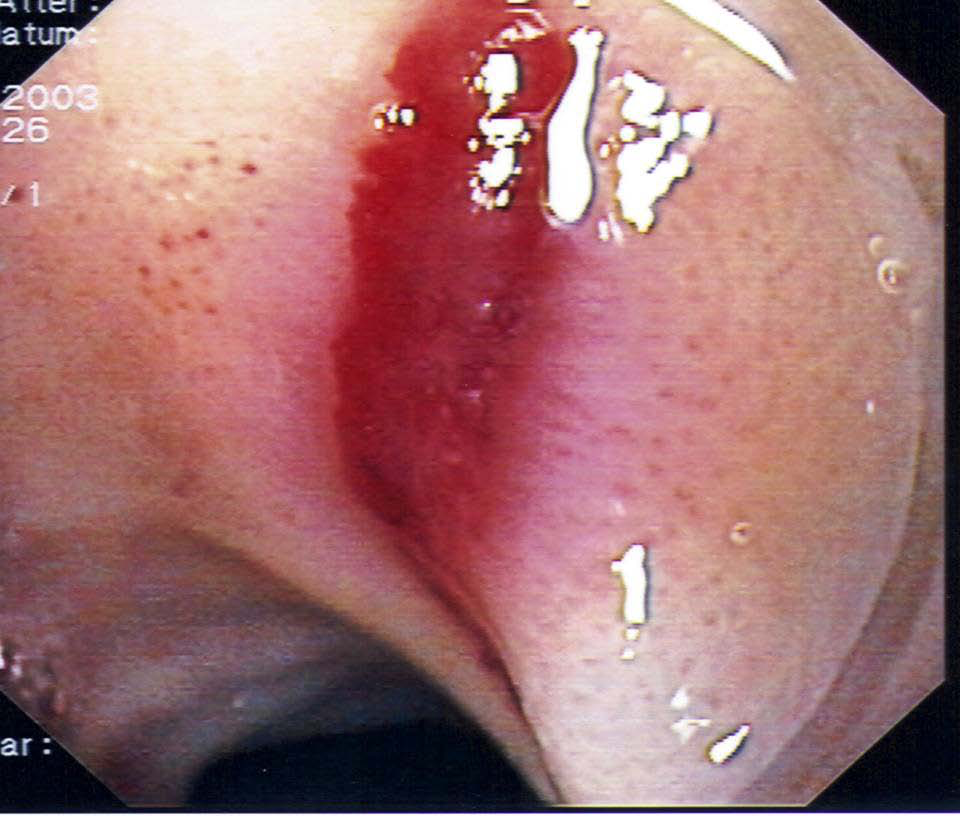

2) Μια ενδοσκοπικη μελέτη (γαστροσκοπηση) χρήσιμη στη διερεύνηση οισοφάγου και στομάχου .

Εικονες απο αξονικη τομογραφια και ενδοσκοπηση

Ταξινόμηση της οισοφαγίτιδας κατά LA

Λύσεις της συνέχειας του βλεννογόνου μικρότερης των 5 mm σε μήκος βαθμός Α , μεγαλύτερης των 5 mm σε μήκος βαθμός Β, λύσεις του βλεννογόνου και των πτυχών σε ποσοστό μικρότερο του 75 % της περιφέρειας του οισοφάγου βαθμός C, διάβρωσεις που εκτείνονται μεγαλύτερα του 75% της περιφέρειας του οισοφάγου βαθμός D.

ευρήματα μη διαβρωτικές και διαβρωτικης οισοφαγιτιδας